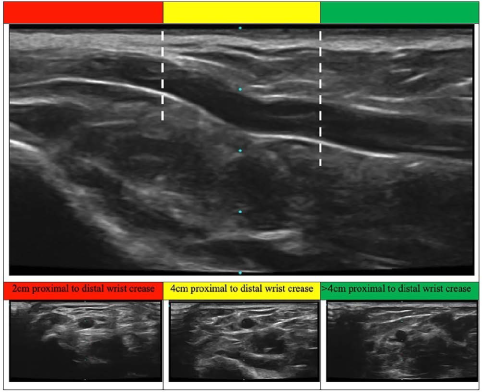

Die ultraschallgestützte Punktion der Radialarterie dient nicht nur der Schonung des Gefäßes, sondern unterstützt auch die gezielte Auswahl einer optimalen Punktionsstelle. Ein strukturierter Ansatz wie die AIM-Methode (Arterial Introduction Method) kann hierbei wertvolle Dienste leisten.

Im Rahmen dieser Methode wird die Radialarterie mithilfe eines hochauflösenden Ultraschallgeräts in einem Bereich etwa 4 cm proximal des Handgelenks untersucht – einer Region, die in der Literatur gelegentlich als „Chi“ (Cheok) bezeichnet wird. In diesem Abschnitt ist die Arterie in der Regel größer kalibriert, tiefer gelegen und weniger durch Gelenkbewegungen beeinflusst. 4

Diese anatomischen Vorteile ermöglichen nicht nur eine höhere Erfolgsrate bei der Kanülierung, sondern auch eine stabilere Katheterlage. Die größere Entfernung zu den Gelenken reduziert das Risiko mechanischer Irritationen und erleichtert die Fixierung des Katheters. Dies wiederum kann die Inzidenz infektiöser und mechanischer Komplikationen senken, die Katheterfunktion verbessern und dessen Liegedauer verlängern.45.